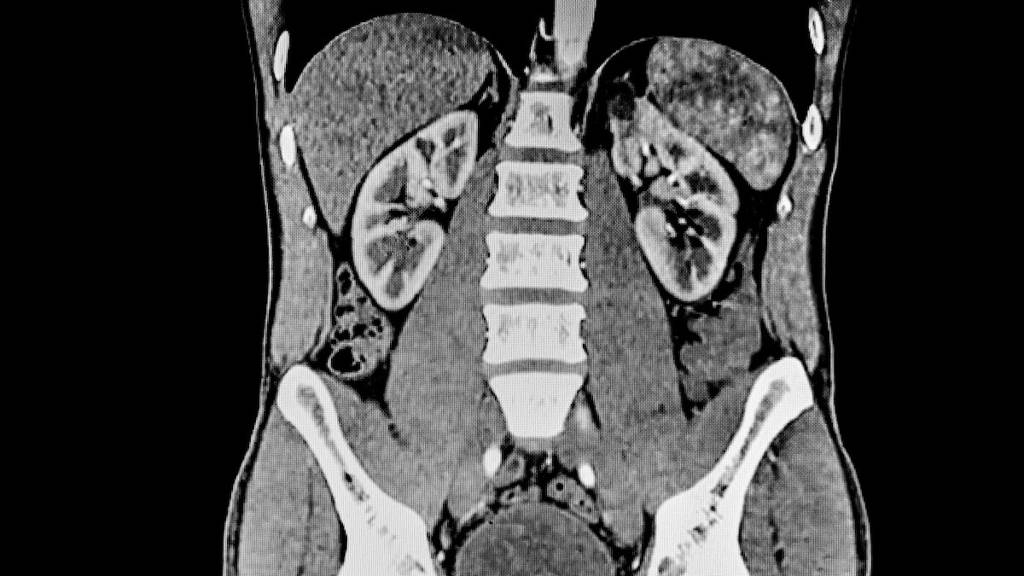

Een onderzoeksteam van de Technische Universiteit München (TUM) heeft een methode ontwikkeld om vroegtijdige nierschade als gevolg van bepaalde kankerbehandelingen te voorspellen. Maanden voordat er een meetbare afname van de nierfunctie gedetecteerd kan worden, beginnen de nieren te krimpen. De onderzoekers zijn erin geslaagd om die trend te detecteren met behulp van een AI-algoritme waarmee CT-scans van de nieren geanalyseerd werden. Daarnaast werden vergelijkbare veranderingen in de milt waargernomen. De nieuwe AI-analyse methode zou er volgens de onderzoekers in de toekomst toe kunnen leiden dat kankerbehandelingen aangepast worden om orgaanschade te voorkomen.

Terwijl factoren zoals de lengte van de nieren of de leeftijd van de patiënt geen betrouwbare voorspellingen opleverden, bleken veranderingen in het niervolume een sterk signaal te zijn: wanneer het niervolume binnen zes maanden na het begin van de behandeling met 10% of meer afnam, was de kans groot dat de nierfunctie binnen nog eens zes maanden aanzienlijk zou afnemen.

“Deze veranderingen in het niervolume zijn heel subtiel. Ze kunnen gemakkelijk over het hoofd worden gezien tijdens routine beeldbeoordelingen omdat artsen zich voornamelijk richten op het opsporen van tumoren en andere belangrijke bevindingen,” legt prof. Matthias Eiber uit, een van de hoofdauteurs van het onderzoek, samen met prof. Rickmer Braren. “Daarentegen kunnen beeldanalyse-algoritmen - mits goed getraind - zelfs deze kleine veranderingen betrouwbaar detecteren,” voegt Dr. Friederike Jungmann toe.